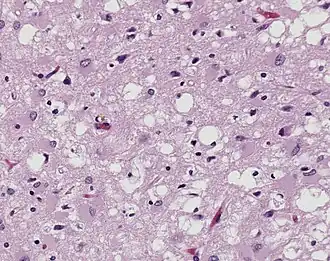

%252C_H%2526E.jpg)

Prions are misfolded proteins that are transmissible and can influence abnormal folding of normal proteins in the brain. They do not contain any DNA or RNA and cannot replicate other than to convert already existing normal proteins to the misfolded state. These abnormally folded proteins are found characteristically in many neurodegenerative diseases as they aggregate the central nervous system and create plaques that damages the tissue structure. This essentially creates "holes" in the tissue. It has been found that prions transmit three ways: obtained, familial, and sporadic. It has also been found that plants play the role of vector for prions. There are eight different diseases that affect mammals that are caused by prions such as scrapie, bovine spongiform encephalopathy (mad cow disease) and Feline spongiform encephalopathy (FSE). There are also ten diseases that affect humans such as, Creutzfeldt–Jakob disease (CJD).[7] and Fatal familial insomnia (FFI).